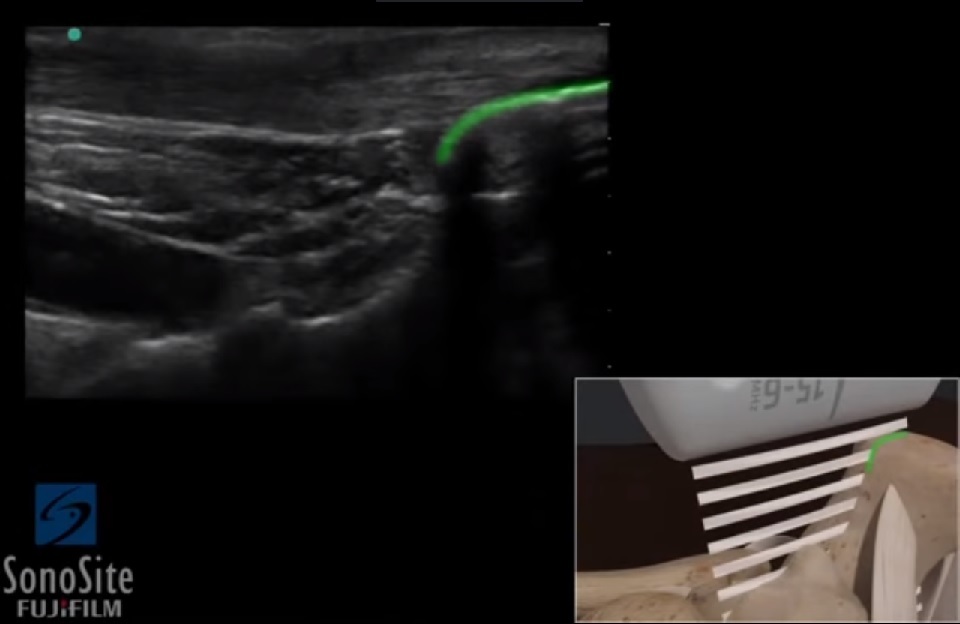

Bild: Fuß und Sprunggelenk, Calcaneus

Markierter Bereich: Oberfläche des Calcaneus